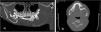

Inicialmente, se solicita una ecografía que muestra imagen quística hipoecogénica, con abombamiento cortical (fig. 1). La ortopantomografía evidencia lesión lítica que afecta a cuerpo y rama mandibular izquierdas y desplaza varios dientes (fig. 2).